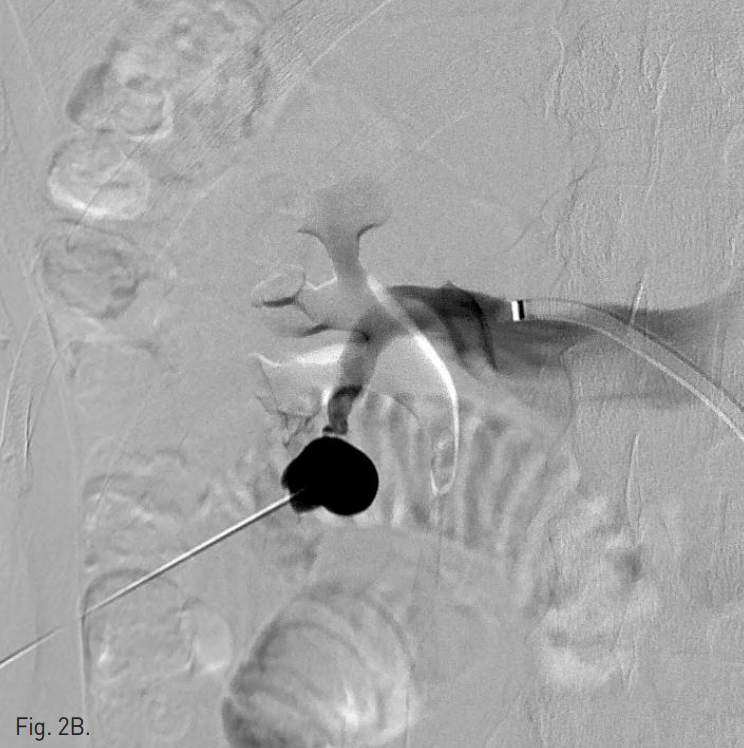

이어 환자를 복와위로 돌려눕히고, 초음파 유도하에 21G Chiba needle로 nidus를 직접 천자 후 혈관조영술을 시행하여 동정맥기 형의 nidus와 유출정맥을 확인하였다(Fig. 2B). Chiba needle을 통하여 3mm × 2cm Tornado coil(Cook, Bloomington, IN)을 nidus에 넣자 유출정맥의 기시부가 매우 좁아서 유출정맥의 입구에 걸려 혈류가 느려졌다. 이후 Gelfoam을 소량 주입하여 혈류가 거의 없어짐을 확인한 뒤, Chiba needle을 nidus의 가장 깊은 위치에서부터 후진시키며, 99% 알코올을 소량씩 주입하여 색전을 시행하였다(Fig. 2C). 색전술 후 시행한 왼쪽 신장동맥 혈관조영술에서 동정맥기형은 더 이상 관찰되지 않는다(Fig. 2D).

Fig. 2

B. Angiogram after direct puncture the nidus of AVM shows the nidus and single draining vein.